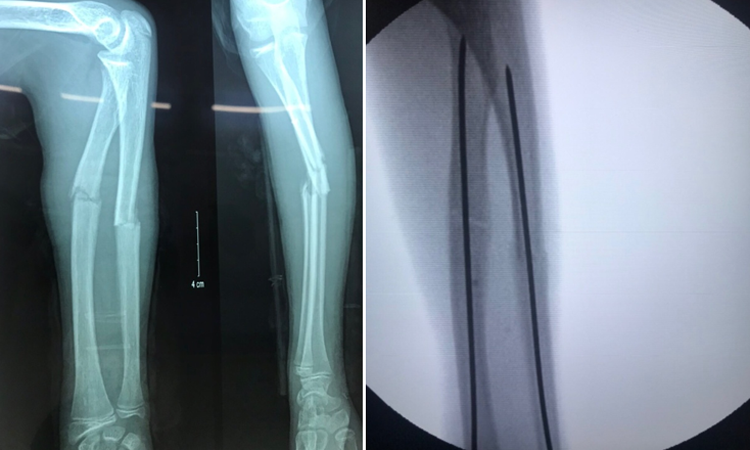

Điều trị gãy 2 xương cẳng tay ở trẻ em bằng kỹ thuật xuyên đinh qua da dưới màn tăng sáng Carm

Khoa Ngoại Chấn Thương- Bệnh viện Trẻ Em Hải Phòng là một trong những đơn vị đi đầu đã triển khai mổ kết hợp xương cẳng tay dưới màn hình tăng sáng C arm. Phương pháp này có nhiều ưu điểm hơn so với mổ mở truyền thống như:

+ Ít tổn hại phần mềm xung quanh, thời gian mổ ngắn, bộc lộ chính xác vị trí ổ gãy, giảm thiểu nguy cơ nhiễm trùng, giảm số ngày nằm viện sau mổ, giảm đau trong mổ và sau mổ tốt, tạo điều kiện tập phục hồi chức năng sớm, bệnh nhân sớm trở lại sinh hoạt bình thường.

+ Có tính thẩm mỹ cao, bệnh nhân không cần bó bột, giảm thiểu biến chứng